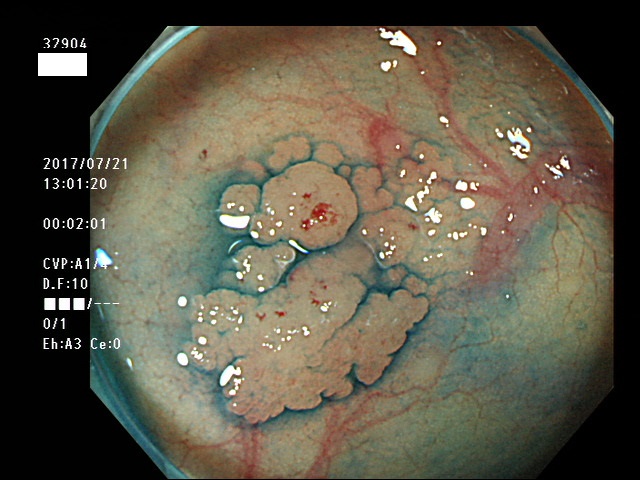

上記100名より抽出した平坦・陥凹型腺腫(=癌化の危険が高いが見落としやすい病変)の内視鏡写真